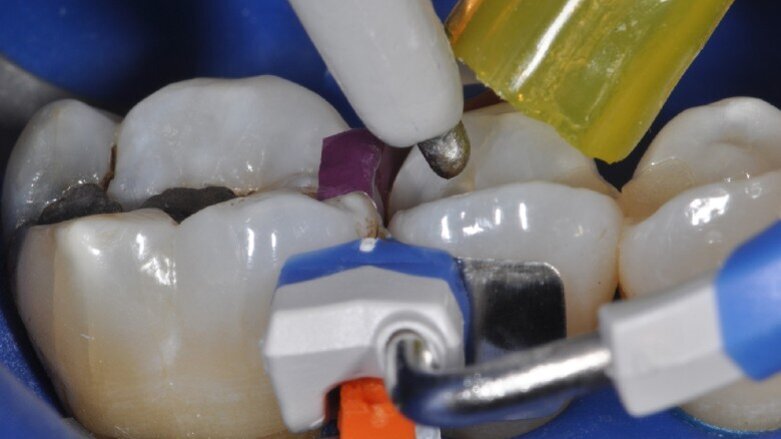

Nella figura 9 è mostrata la visione vestibolare dopo la fase di applicazione del bonding, che viene steso con un leggero soffio d’aria e contemporaneamente aspirato per favorire la fuoriuscita degli eccessi. La fase adesiva termina con la polimerizzazione di un sottile strato di composito fluido (Fig. 10).Successivamente viene ricostruita la parete interprossimale e la cresta marginale con un unico apporto di composito (Fig. 11). La figura 12 illustra il restauro al termine della stratificazione e dell’applicazione del supercolore, con la rimozione dell’anello separatore dopo la polimerizzata della parete interprossimale. Nella figura 13 possiamo vedere il restauro al termine della sgrossatura e rifinitura con dischetti abrasivi, frese diamantate 40 micron e gommini browny; si noti come la cresta marginale sia facilmente rifinibile grazie alla guida della matrice anatomica, senza che l’area di contatto venga toccata dagli strumenti.